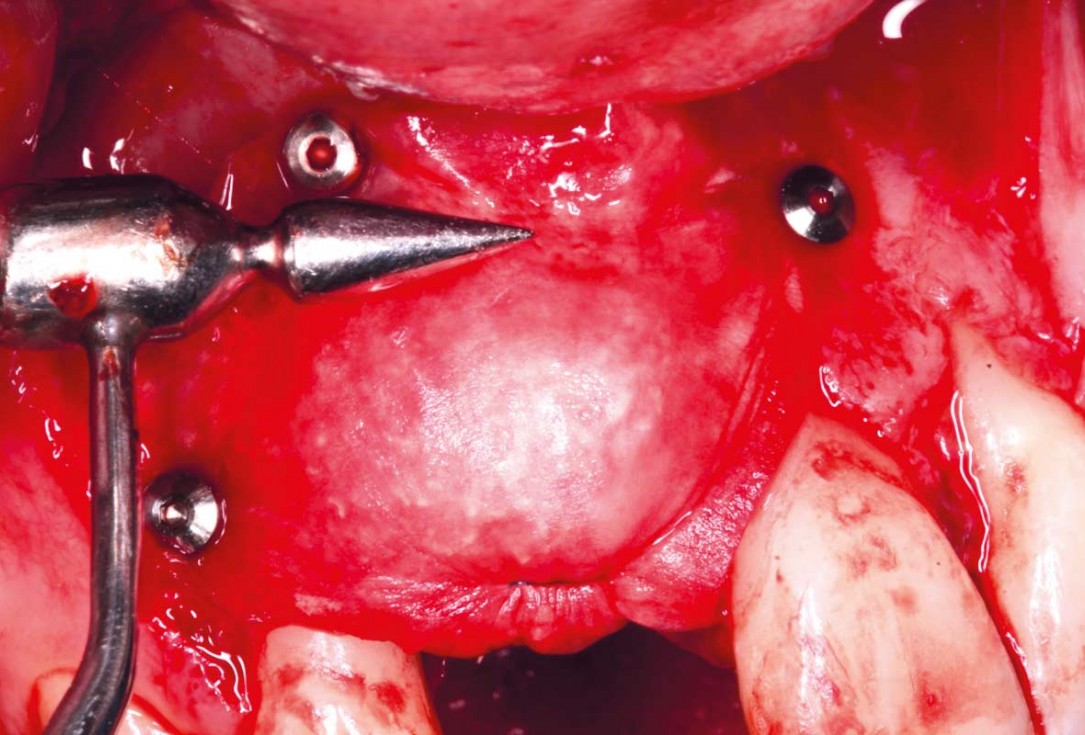

05/20 - Stabilisation of Jason® membrane using additional titanium pins.Delayed implant placement with GBR and soft tissue augmentation at the aesthetic area - 2 years follow up – Dr. H. Maghaireh & Dr. V. Ivancheva

06/20 - Grafting site was covered by two mucoderm® (15x20mm) used as a soft tissue graft as well as a membrane over Jason® membrane . mucoderm® was stabilised with sutures on each side.Delayed implant placement with GBR and soft tissue augmentation at the aesthetic area - 2 years follow up – Dr. H. Maghaireh & Dr. V. Ivancheva